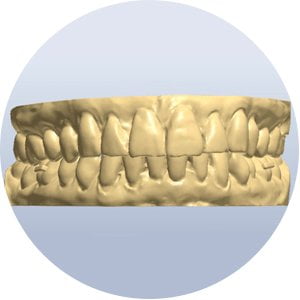

An intra-oral 3D scan or a conventional impression which will be later 3D scanned extra-orally will be used to plan your orthodontic treatment analysis and planning.

A 3D imaging software will be used to plan the accurate teeth alignment and later to 3D print the planned models and clear aligners to fit over your teeth and help in the 3d planned teeth alignment.